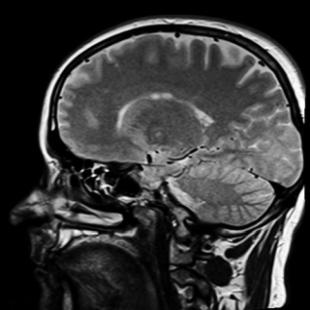

The key to the technique's success lies in alpha waves - tiny natural oscillations in brain electrical activity of between 7.5 and 12.5 hertz which have long been associated with relaxation and mood.

Alpha waves from the front of the brain are known to be connected with placebo analgesia and may influence how other parts of the brain process pain, so the team investigated what kinds of external stimuli would increase alpha power and heighten the beneficial effects.